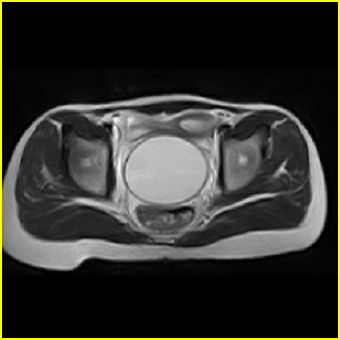

女、15岁、下腹疼痛2天,排尿困难1天。查体:处女膜闭锁,距处女膜约4至5cm处扪及一约5cm直径的圆形包块,张力较高,触痛明显、欠活动。b超提示子宫增大伴宫内增强回声团。

影像意见:子宫直肠陷凹积血。

更正影像意见:阴道积血。

处女膜闭锁,阴道积血

处女膜闭锁,阴道积血,子宫积血.

先天性处女膜闭锁,伴阴道积血,不除外先天性阴道粘液囊肿形成。

阴道积血,子宫积血.

子宫及阴道积血。

处女膜闭锁,伴子宫及阴道积血.